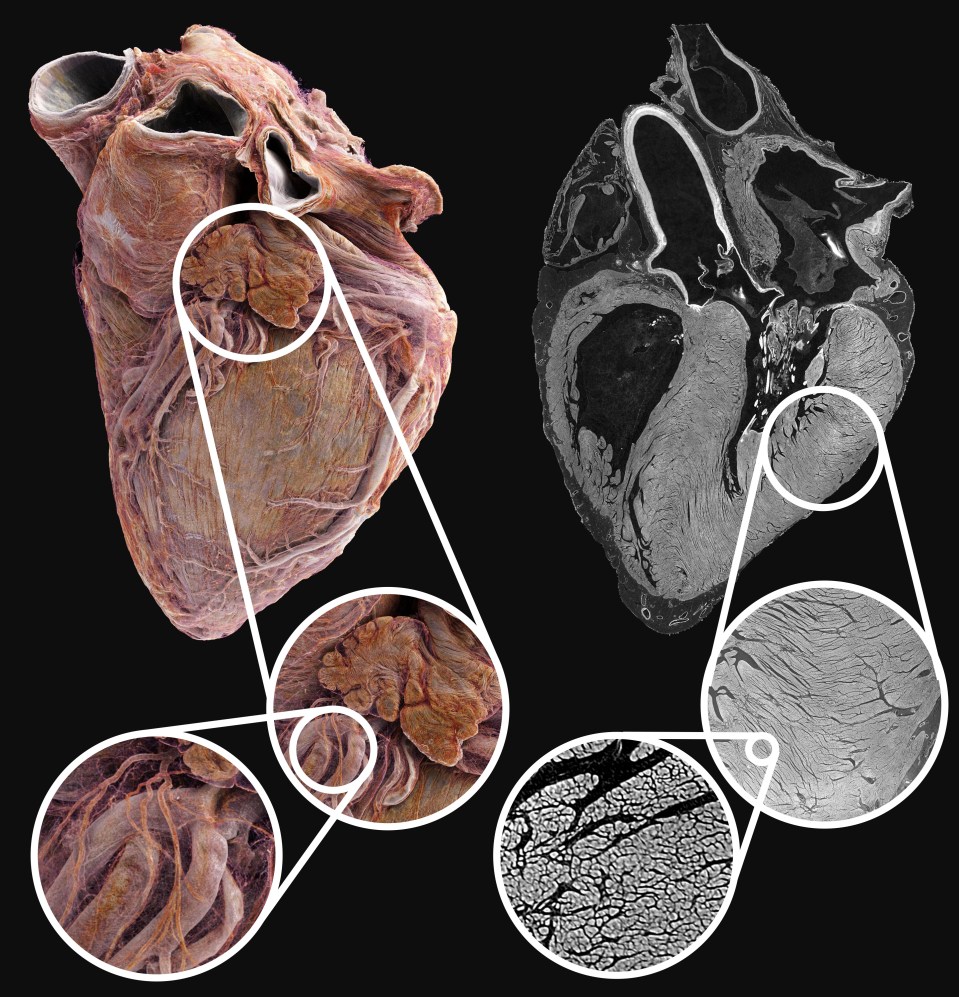

Lekári zvyčajne používajú zobrazovacie techniky, ako je ultrazvuk, CT a MRI, na diagnostiku kardiovaskulárnych ochorení, ale tie neposkytujú podrobné štrukturálne informácie o tom, čo sa deje v orgáne. Teraz vedci vytvorili prvý atlas ľudského srdca na svete, ktorý pripomína Google Earth a ponúka bezprecedentný pohľad do zdravého a chorého srdca. Technológia poskytuje podrobné snímky až do hĺbky 20 mikrometrov, čo umožňuje 3D pohľad na celý orgán so zobrazením na úrovni buniek v určitých oblastiach.

Tento prelomový objav by mohol priniesť revolúciu v chápaní a liečbe kardiovaskulárnych ochorení vrátane arytmie. Pomocou prelomovej röntgenovej techniky nazvanej hierarchická fázová kontrastná tomografia (HiP-CT) vedci z University College London a Európskeho zariadenia pre synchrotrónové žiarenie (European Synchrotron Radiation Facility – ESRF), čo je najjasnejší röntgenový zdroj na svete vo francúzskom Grenobli, neuveriteľne podrobne zobrazili dve celé srdcia dospelých ľudí.

Táto technológia ponúka globálny pohľad na orgán a odhaľuje štruktúry a spojenia, ktoré predtým neboli známe. Cieľom štúdie je zlepšiť možnosti liečby a chirurgického výcviku poskytnutím realistických modelov srdca. Zobrazovanie každého srdca vygenerovalo 10 terabajtov údajov, čo je miliónkrát viac ako pri štandardnom CT vyšetrení.

Napriek výzvam spojeným so spracovaním veľkého množstva údajov zostáva zobrazovanie kompletných dospelých ľudských sŕdc pomocou HiP-CT v ESRF bezkonkurenčné. Táto technológia má potenciál zmeniť kardiovaskulárnu medicínu tým, že umožní výskumníkom študovať vznik porúch srdcového rytmu a efektívne vyhodnocovať stratégie liečby.